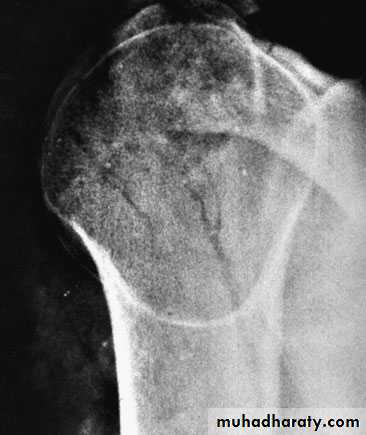

X-Ray:

The anteroposterior x-ray will show the overlapping shadows of the humeral head and glenoid fossa, with the head usually lying below and medial to the socket.A lateral view aimed along the blade of the scapula will show the humeral head out of line with the socket.

AP film (like an electric light bulb), (the ‘empty glenoid’ sign).A lateral film and axillary view is essential; it shows posterior subluxation or dislocation and sometimes a deep indentation on the anterior aspect of the humeral head.